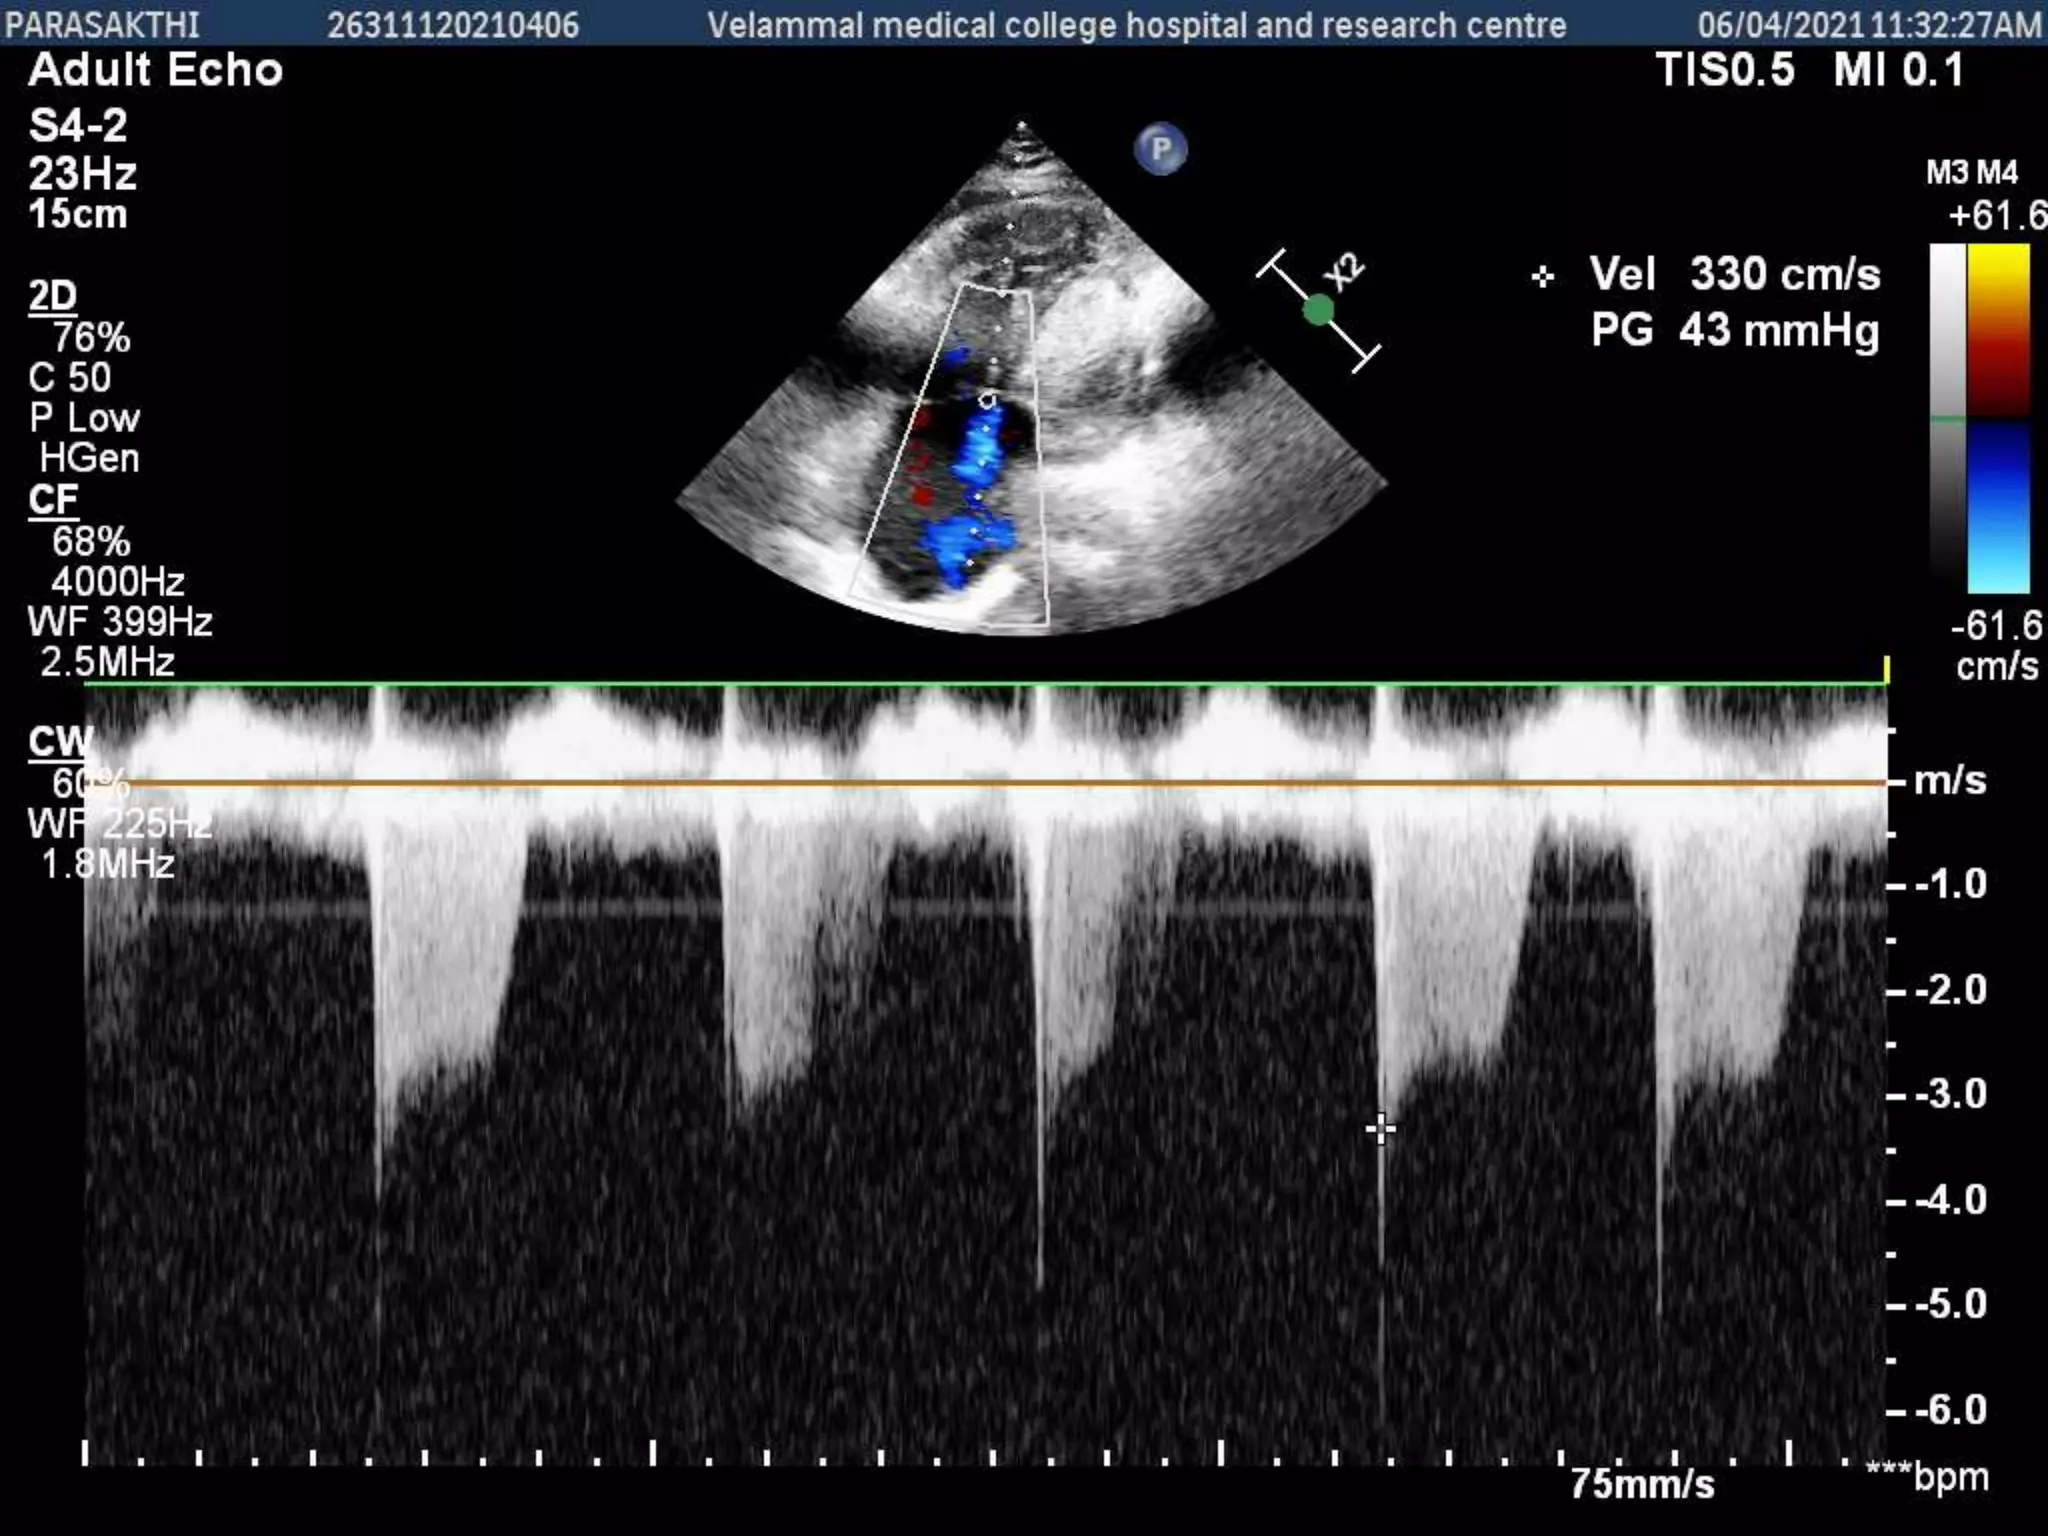

Evaluation of pulmonary artery

pressure

• Pulmonary pressures should be assessed in all patients with

ASDs.

• RV and pulmonary artery systolic pressures are estimated

using Doppler echocardiography by obtaining the peak

tricuspid regurgitation continuous-wave Doppler signal,

using the modified Bernoulli equation, and adding the

estimated right atrial pressure

Evaluation of pulmonaryartery pressure • Pulmonary pressures should be assessed in all patients with ASDs. • RV and pulmonary artery systolic pressures are estimated using Doppler echocardiography by obtaining the peak tricuspid regurgitation continuous-wave Doppler signal, using the modified Bernoulli equation, and adding the estimated right atrial pressure • RV volume overload is suggested by diastolic flattening of the interventricular septum • RV pressure overload is suggested by systolic (or systolic and diastolic) flattening of the interventricular septum